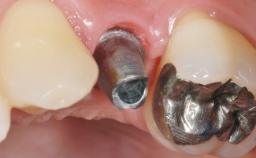

Early Placement of an Implant in a Maxillary Right Central Incisor Site

Type of Implants Two-Piece

Attachment Two-Piece

Abutment Type Customized

Prosthesis Type FDP